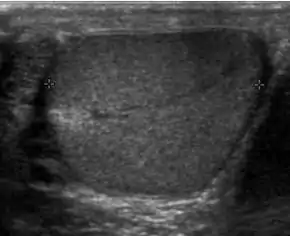

Fibrotic striations

Fibrotic striations.

A striated pattern of the testicle, radiating from its mediastinum, does not have clinical importance unless there are alarming symptoms or abnormal signal on Doppler ultrasonography.[6] It is presumed to represent fibrosis.[6]